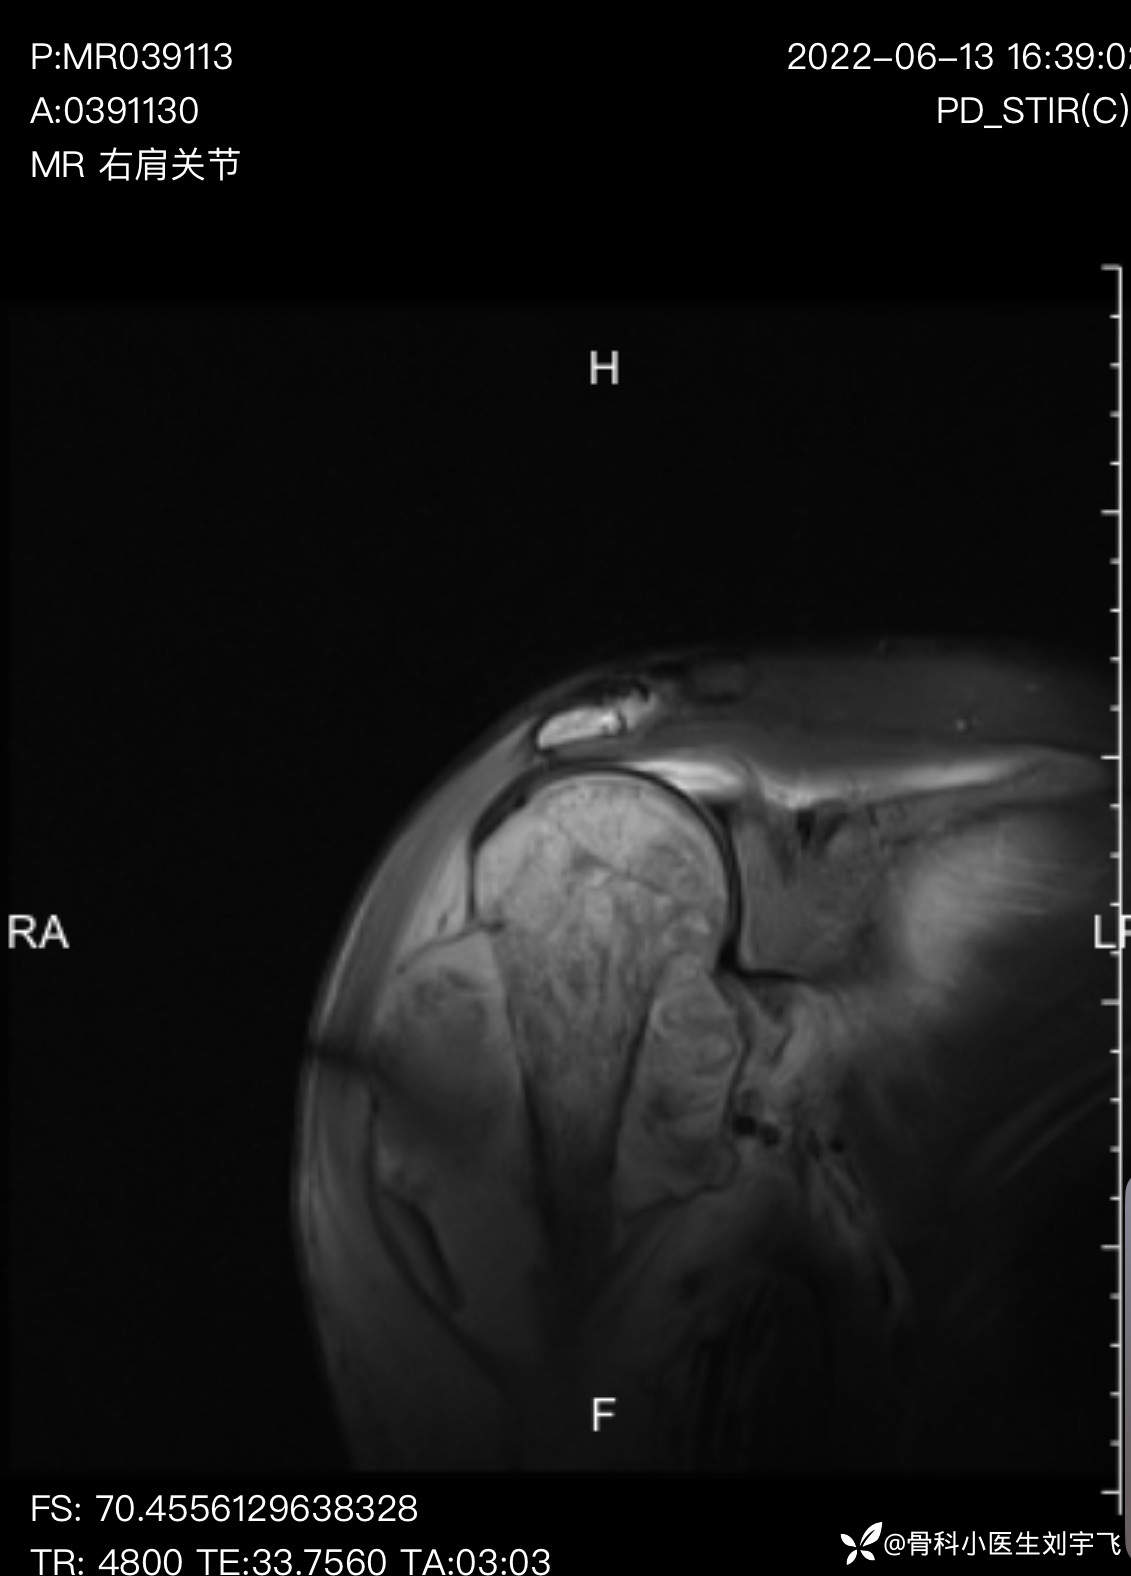

我感觉不对,理论上轻微的损伤不应该诊断肿啊,然后再次观察X线发展了问题(这时候我真想踹自己一脚)明明书上见了这么多,怎么就漏诊了,当然,我还是抱着侥幸的态度可能是良性的,继续做核磁,做了核磁,我给我的老师打了电话(知名的一位专家)老师的诊断让我心里咯噔一下,老师说骨膜反应,不像良性东西,然后我给患者建议上级医院治疗,就是找我的老师看看。

X线示:肱骨近端骨内正常骨小梁或骨皮质消失,取而代之的是密度较高的团状占位,在长骨表面可见各种异常增厚的骨膜。

骨膜反应典型的Codman三角

初步诊断骨肉瘤

建议患者进一步行MRI检查及病理活检进一步确认。